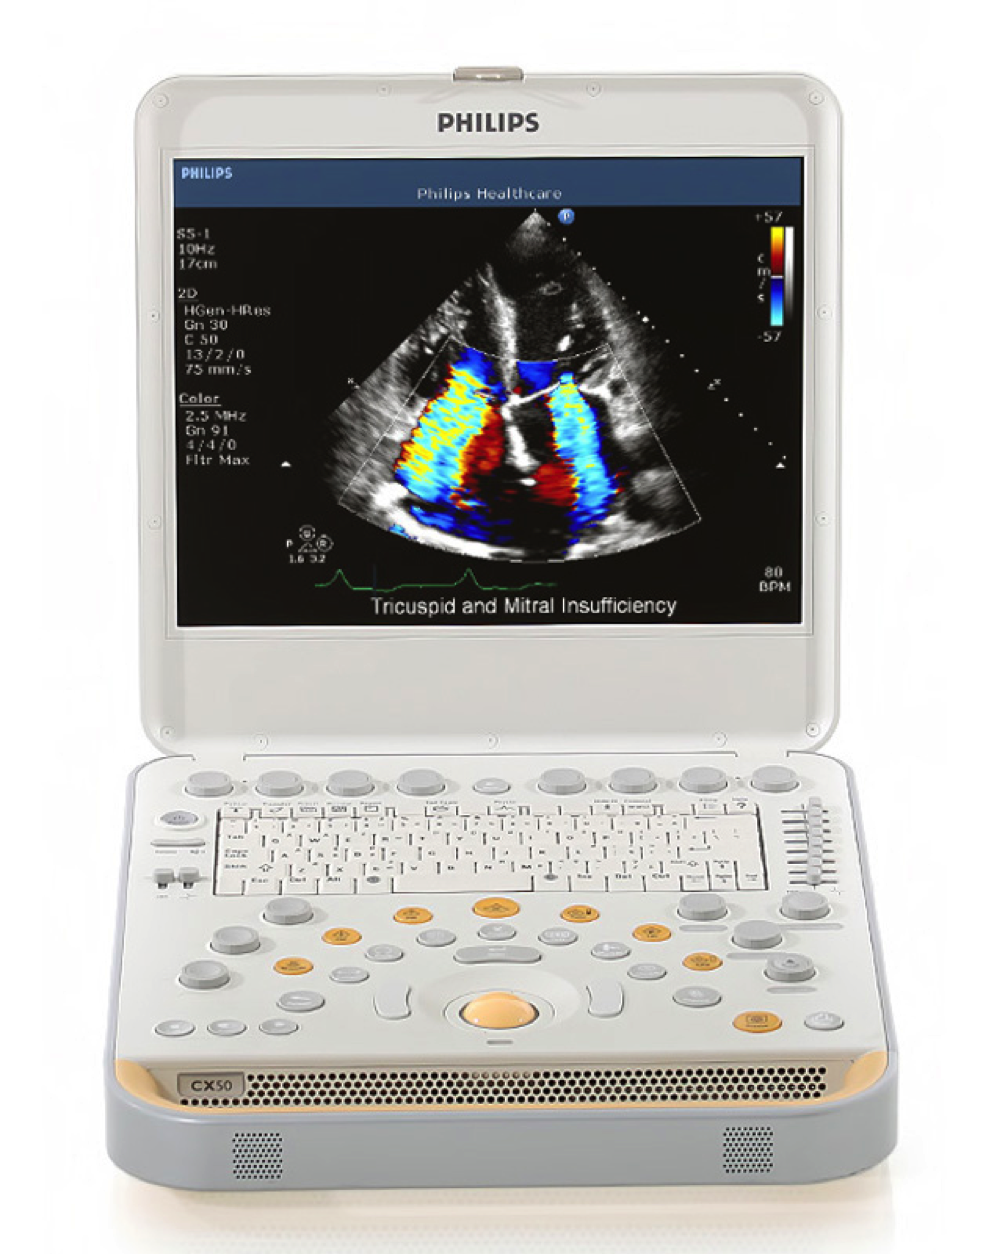

ecografo PHILIPS CX 50 xmatrix

Per intervenire rapidamente è necessario un sistema ecografico portatile Non è semplice riuscire a ottenere dati diagnostici da esami effettuati con sistemi portatili. Con CX50 ora potrete avere ovunque la qualità necessaria per formulare diagnosi affidabili. È il sistema ecografico stesso ad andare dal paziente e può essere trasportato anche in sala operatoria, unità coronarica, unità di terapia intensiva, anche neonatale o pediatrica, presso ambulatori di screening o al pronto soccorso. La qualità delle immagini di CX50 lo rende ideale per i pazienti in condizioni critiche, quando lo spazio è limitato dalla presenza di molte apparecchiature e servono risposte rapide.